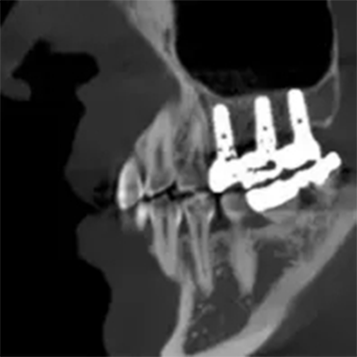

T-MAR Metal Artifact Reduction

T-MAR Metal Artifact Reduction in LargeV Dental CBCT

With the new T-MAR module, the system automatically removes metal artifacts and corrects image distortions intelligently.

Hence, the final images remain clear, accurate, and clinically reliable.